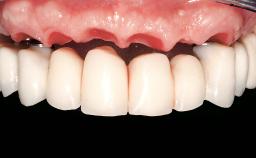

Immediate Loading of Eight Implants in the Maxilla and Six Implants in the Mandible and Final Restoration with Three-Unit and Four-Unit FDPs

Prosthesis Type FDP

Defining Characteristics Fully edentulous upper jaw to be rehabilitated with an implant-borne fixed dental prosthesis

Loading Protocol Immediate

Occlusal Scheme/Issues Anterior guidance